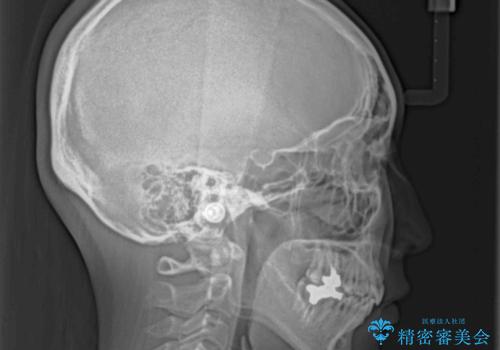

- 前歯のデコボコを気にして来院された患者様です。

非抜歯矯正にて治療を行うと、仕上がりで口元が突出する可能性があったため、小臼歯抜歯での矯正治療を行うこととしました。

上顎は左右の第一小臼歯2本を、下顎は左右の第二小臼歯2本を抜歯して、口元が突出しないようにしながら、奥歯の咬み合わせを改善していく治療計画としました。

目立たない装置が希望であったため、上顎が裏側装置である、ハーフリンガル装置を選択されました。

第二小臼歯抜歯としたため、治療期間は長くなりましたが、満足のいく仕上がりとなりました。